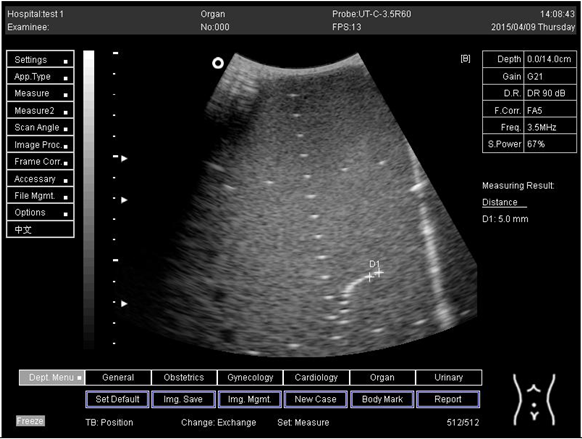

14.0Axial resolution

Biomimetics 07 00130 i023

D1 = 4.9

D2 = 4.2

Lateral resolution

Biomimetics 07 00130 i024

D1 = 5.0